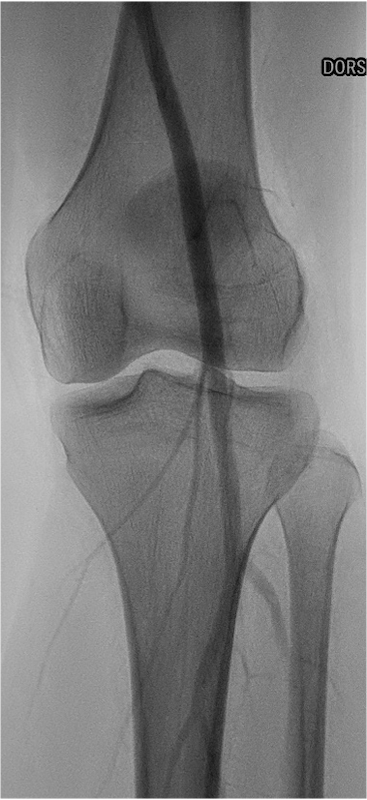

Popliteal entrapment syndrome is a rare condition in which the popliteal artery, which supplies blood to the lower leg and foot, is compressed or squeezed by nearby structures, such as the muscles and tendons at the back of the knee. This can cause reduced blood flow to the lower leg and foot, leading to pain, numbness, weakness, and other symptoms. It is most commonly seen in young athletes and can be treated with surgery or other interventions aimed at relieving the compression of the artery.